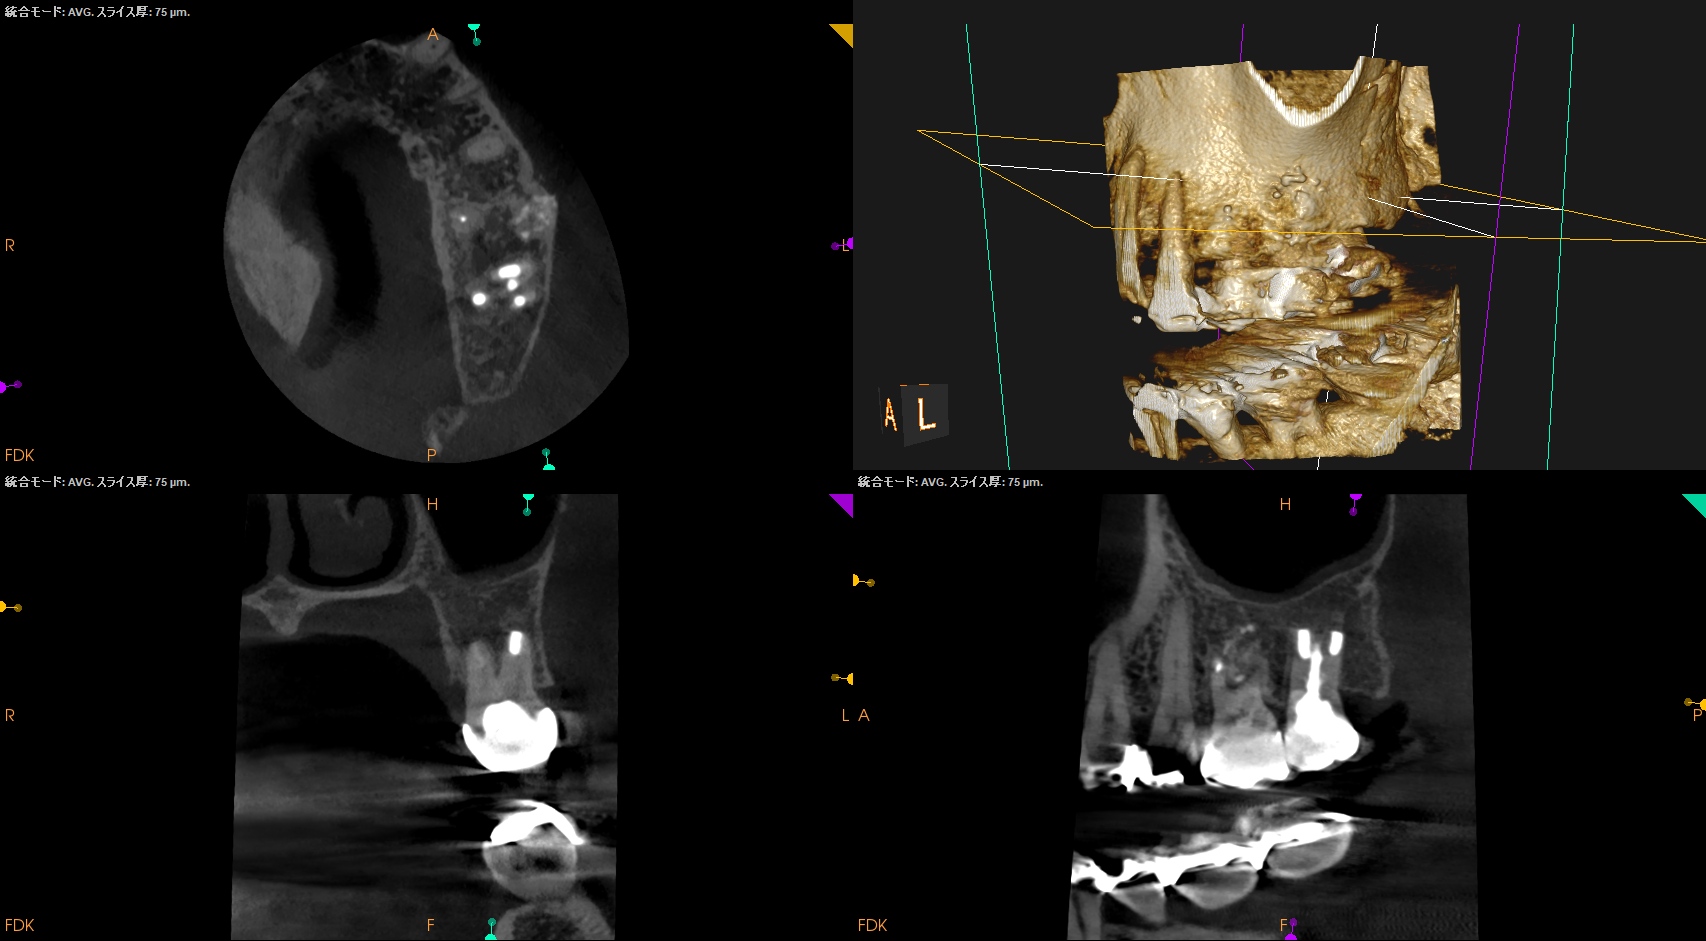

CBCT(2025.11.5)

MB

DB

P

Perforation site

治療前/直後と1年後を比較した。

完治だ。